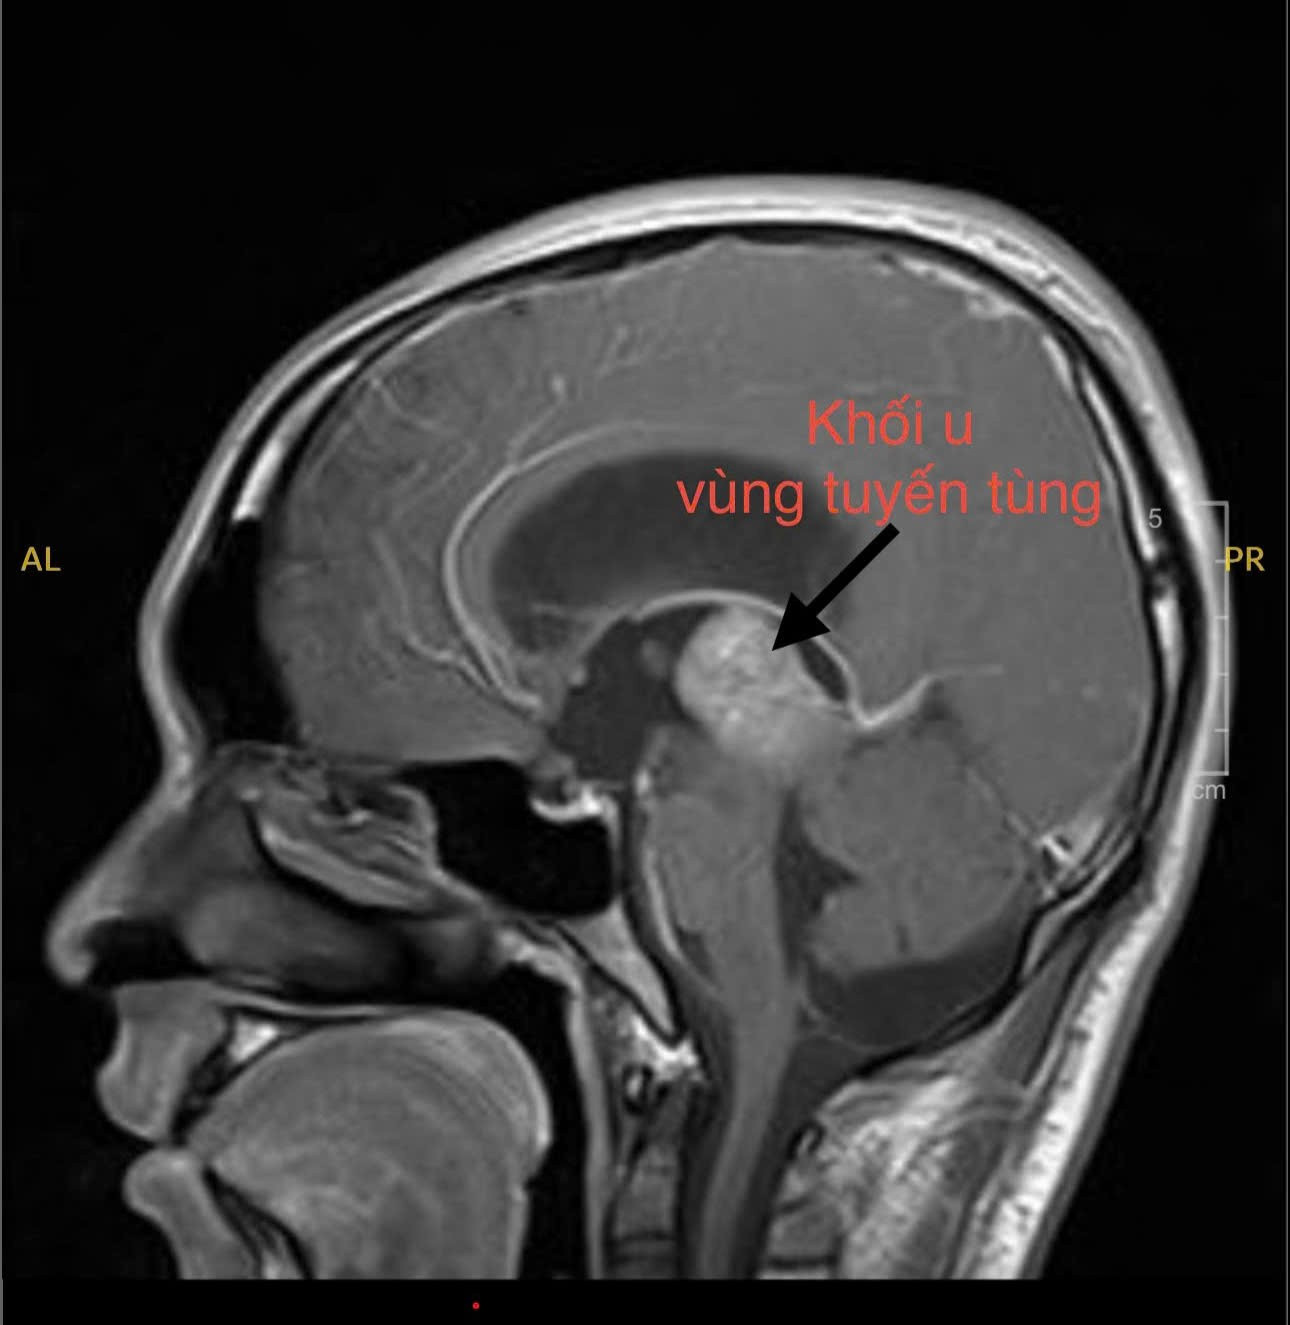

Trên hình ảnh kiểm tra, bác sĩ phát hiện khối u nằm sâu ở vị trí trung tâm não của người bệnh

Nhận thấy tình trạng bất thường, người mẹ đã đưa con đến cơ sở y tế địa phương thăm khám. Tại đây, bác sĩ chỉ định chụp MRI não. Hình ảnh ghi nhận một khối u vùng tuyến tùng – vị trí nằm sâu giữa não, có thể gây chèn ép đường lưu thông dịch não tủy. Theo bác sĩ, đây chính là nguyên nhân khiến áp lực nội sọ của H. tăng cao, dẫn tới đau đầu dữ dội và các rối loạn kèm theo.